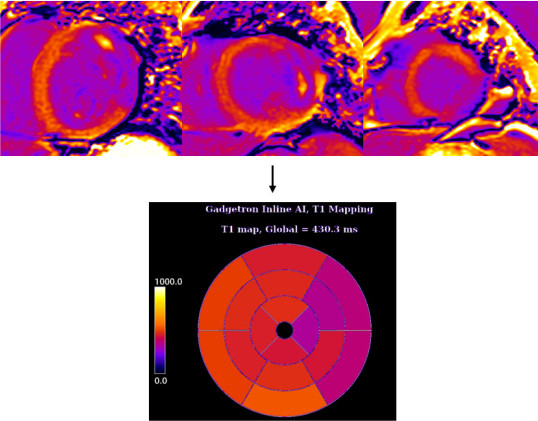

T1 and T2 mapping

T1 and T2 mapping allows quantitative analysis of tissue characteristics on cardiac MRI scans so that doctors can better identify diseases. However, these measurements can be difficult and time consuming to make. James has developed a system to automated this process and it is now in use at two Hospitals.